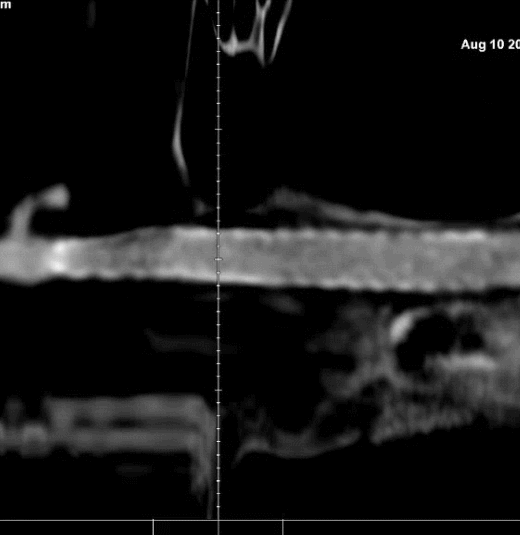

🔆  MRI+MRA检查:脑内散在少许腔隙性脑梗塞及小缺血灶。轻度脑白质疏松症;脑萎缩。脑动脉硬化伴双侧大脑后动脉、颈内动脉节段性狭窄。双侧颈内动脉C5段突起影,动脉瘤可能。

MRI+MRA

脑血管造影(主动脉弓造影及后循环)

右侧颈动脉造影

左侧颈动脉造影

左侧颈内动脉重建(左侧狭窄及扩张较右侧更甚)

术前                         术后3个月